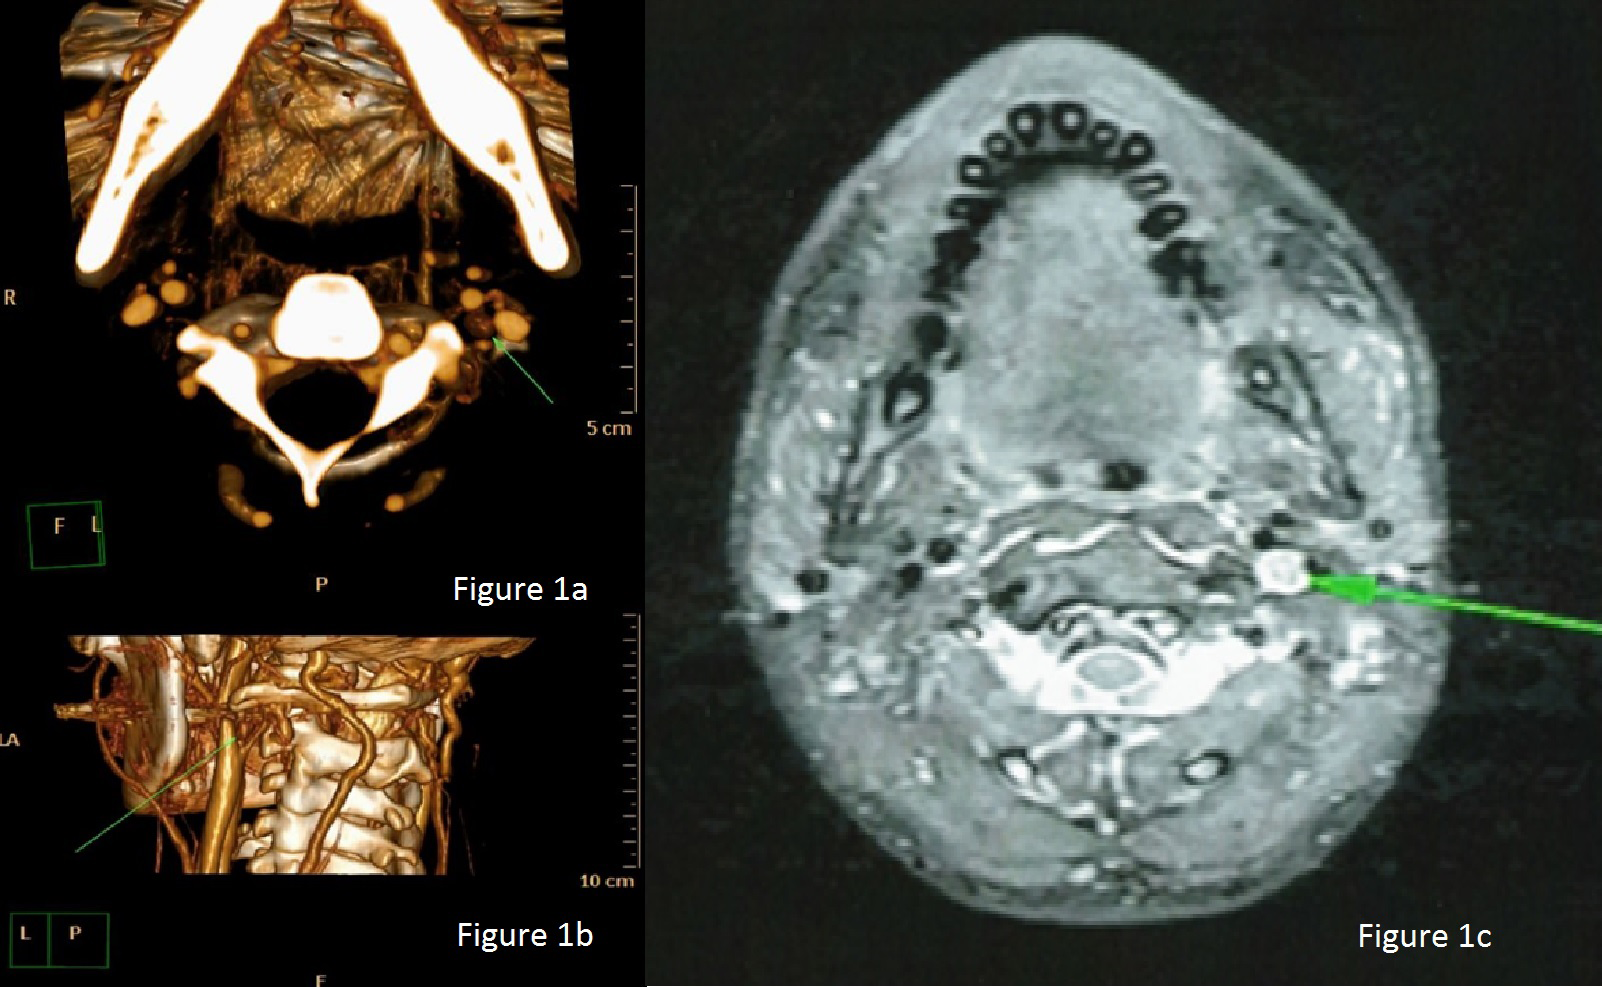

Although rare, intravagal parathyroid adenomas do occur. Therefore, examination of the vagus nerve should be strongly considered when four normal glands are found, as intravagal adenomas appear to represent accessory ectopically located parathyroid tissue in patients with persisting high calcium level post four-gland parathyroidectomy. Our experience serves to emphasize that, in re-operative parathyroid surgery, preoperative localization of the offending parathyroid gland is critical. This should include selective venous sampling to identify the sight of the missed gland. Formal CT and MRI can identify site of parathyroid adenomas. Finally, CT or USS guided FNA allows the surgeon to histopathologically confirm the offending parathyroid gland prior to surgery (Figures 1a-1c, 2 & 3).

Figure 1a 3D-reconstructed Axial Computed Tomography Angiogram image demonstrating a small mass in the left carotid triangle.

Figure 1b  3D reconstructed image of a Computed Tomography Angiogram showing the mass posterior to the left internal carotid artery.

Figure 1c  Axial contrast-enhanced T1-weighted Magnetic Resonance Imaging shows an avidly enhancing mass in the left carotid space.